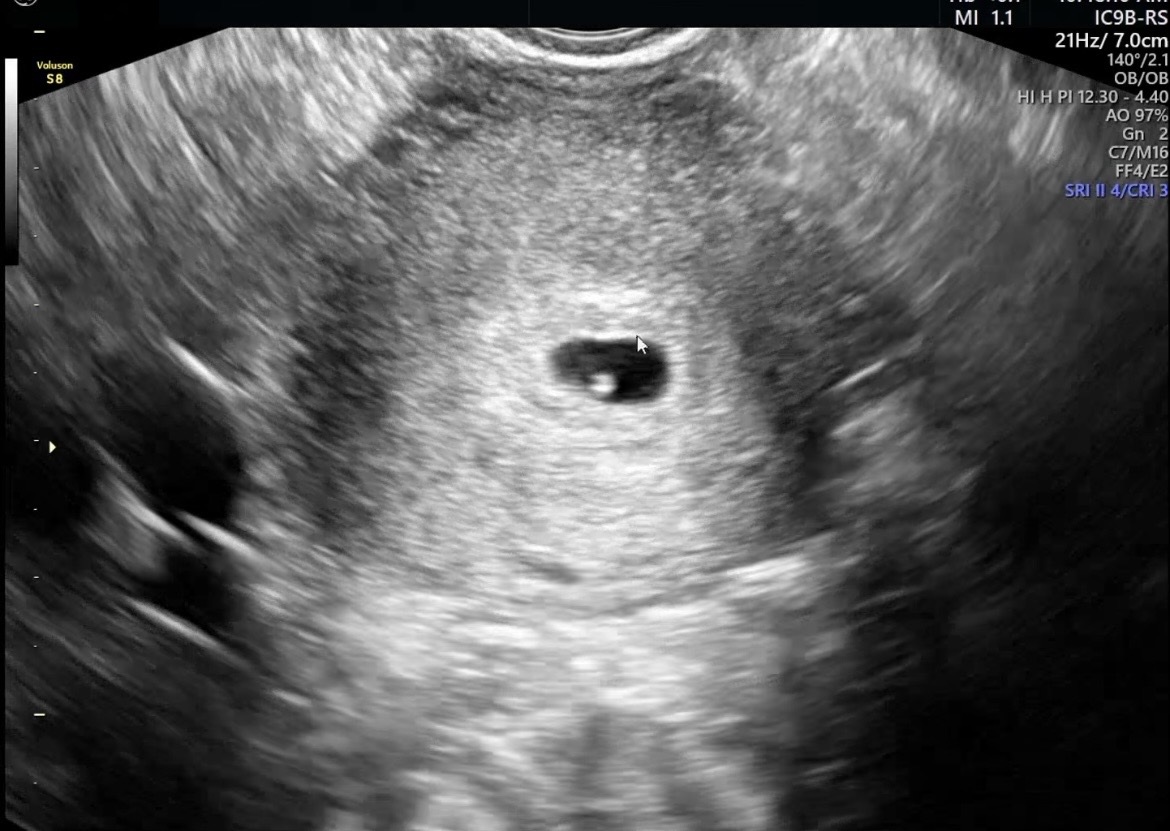

| 가슴 떨리는 임신 이야기를 공유해 주세요. | 1년 이상 자연임신이 되지 않아 고민하던 중, 한 분의 진실성 있는 네이버 리뷰를 보고 망설임 없이 서울아이비에프여성의원에 내원하게 되었습니다. 이유정 원장과의 첫 진료에서 “내가 잘 찾아왔구나”라는 확신이 들었고, 이곳에서 될 때까지 도전해봐야겠다고 마음먹었습니다. 인공수정 2회 후 시험관 1차에 임신에 성공했고, 2026년 저에게는 그 어떤 값비싼 선물보다도 더 소중한 순간이었습니다. |

| 치료 도중 느꼈던 가장 기뻤던 순간과 절망적인 것들은 무엇인가요? 잊지 못할 경험이 있나요? | 인공수정이 반복적으로 잘 되지 않았지만, “도전하다 보면 꼭 되겠다”는 마음가짐 덕분에 절망하지 않고 치료를 이어갈 수 있었습니다. 가장 기뻤던 순간은 아이의 심장 소리를 처음 들었을 때로, 안도감과 행복감이 동시에 밀려왔던 순간이었습니다. |